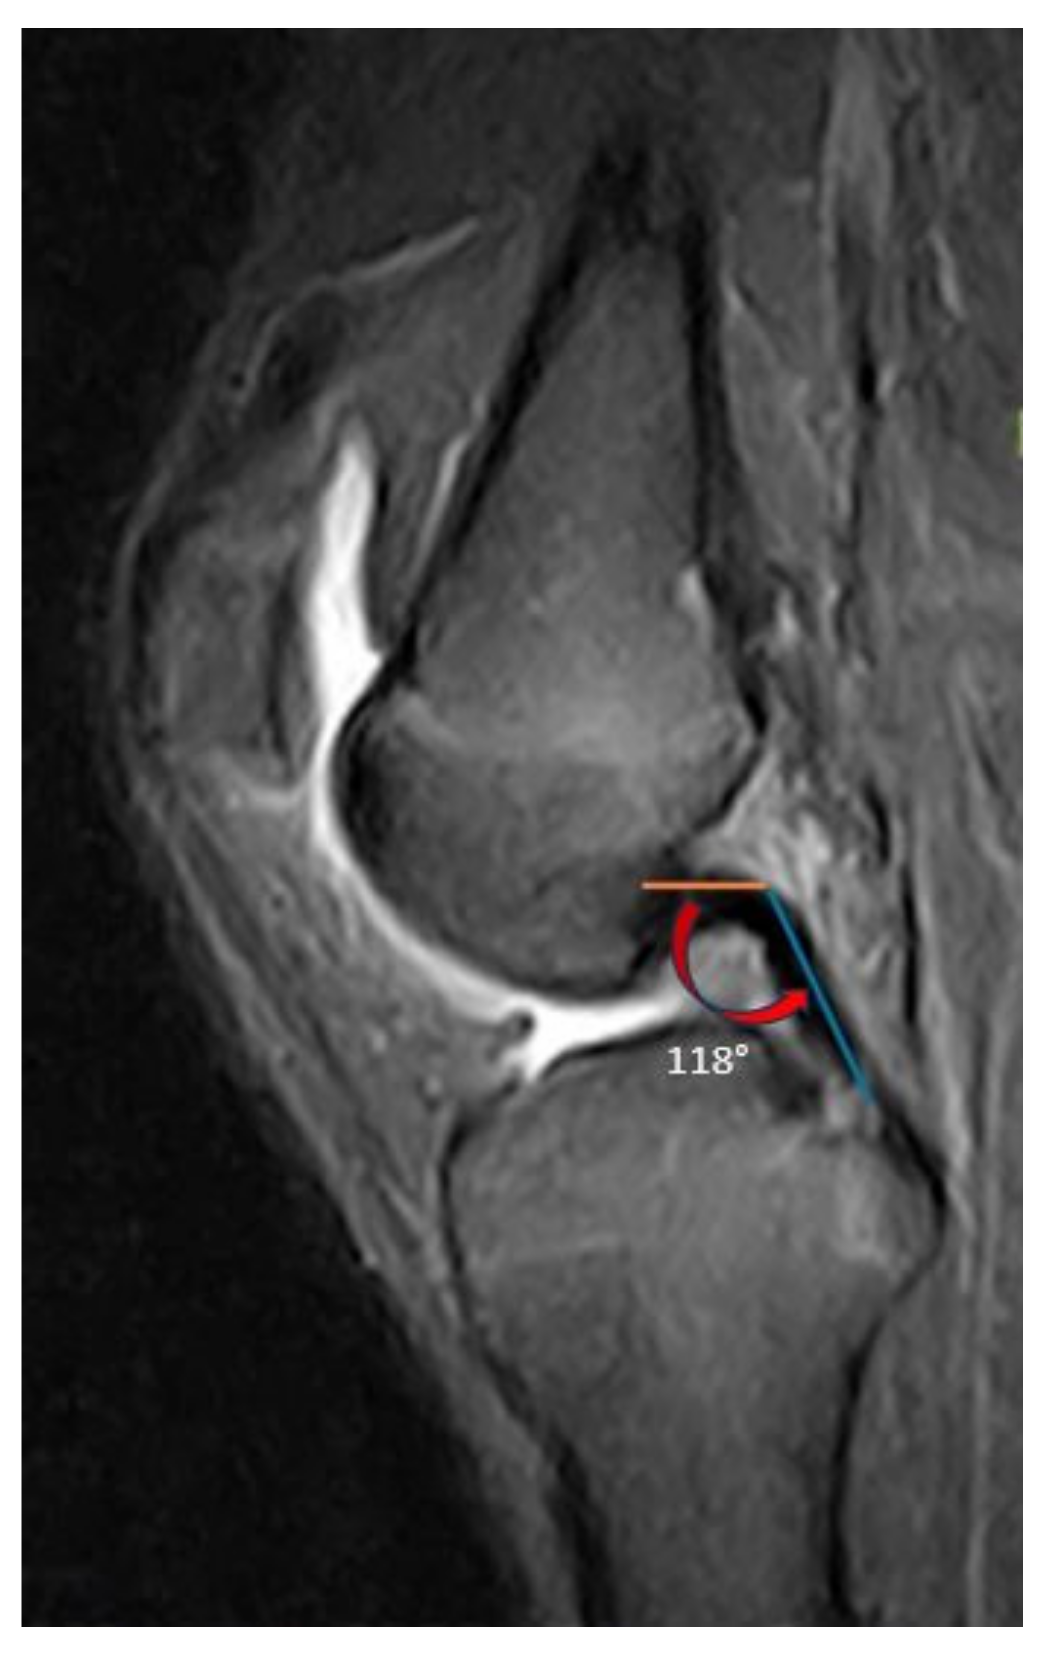

2.4. Radiological Assessment

| PCL buckling angle | 125 ± 12.9 (97–154) |

| PCL buckling angle | 125.7 ± 12.4 (97–154) | 123.8 ± 13.8 (97.5–144) | 0.495 | −3.601 to 7.401 | 2.771 |